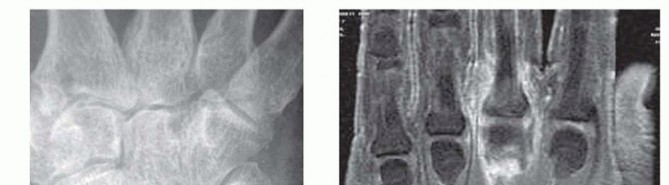

Radiographic evaluation begins with orthogonal plain films. Early in the disease process, radiographs are typically normal or demonstrate only subtle soft tissue swelling and joint space widening secondary to effusion. However, they are crucial for ruling out retained radiopaque foreign bodies, fractures, or underlying chronic arthropathies. The presence of chondrocalcinosis, for instance, may suggest pseudogout, though crystalline arthropathy and septic arthritis can coexist.

Image

When the diagnosis remains equivocal, or to assess the extent of soft tissue and osseous involvement, Magnetic Resonance Imaging (MRI) is the modality of choice. MRI provides unparalleled soft tissue contrast, readily identifying joint effusions, synovial hypertrophy, and early marrow edema indicative of impending osteomyelitis. T2-weighted fluid-sensitive sequences will dramatically highlight the intra-articular purulence and surrounding inflammatory edema.